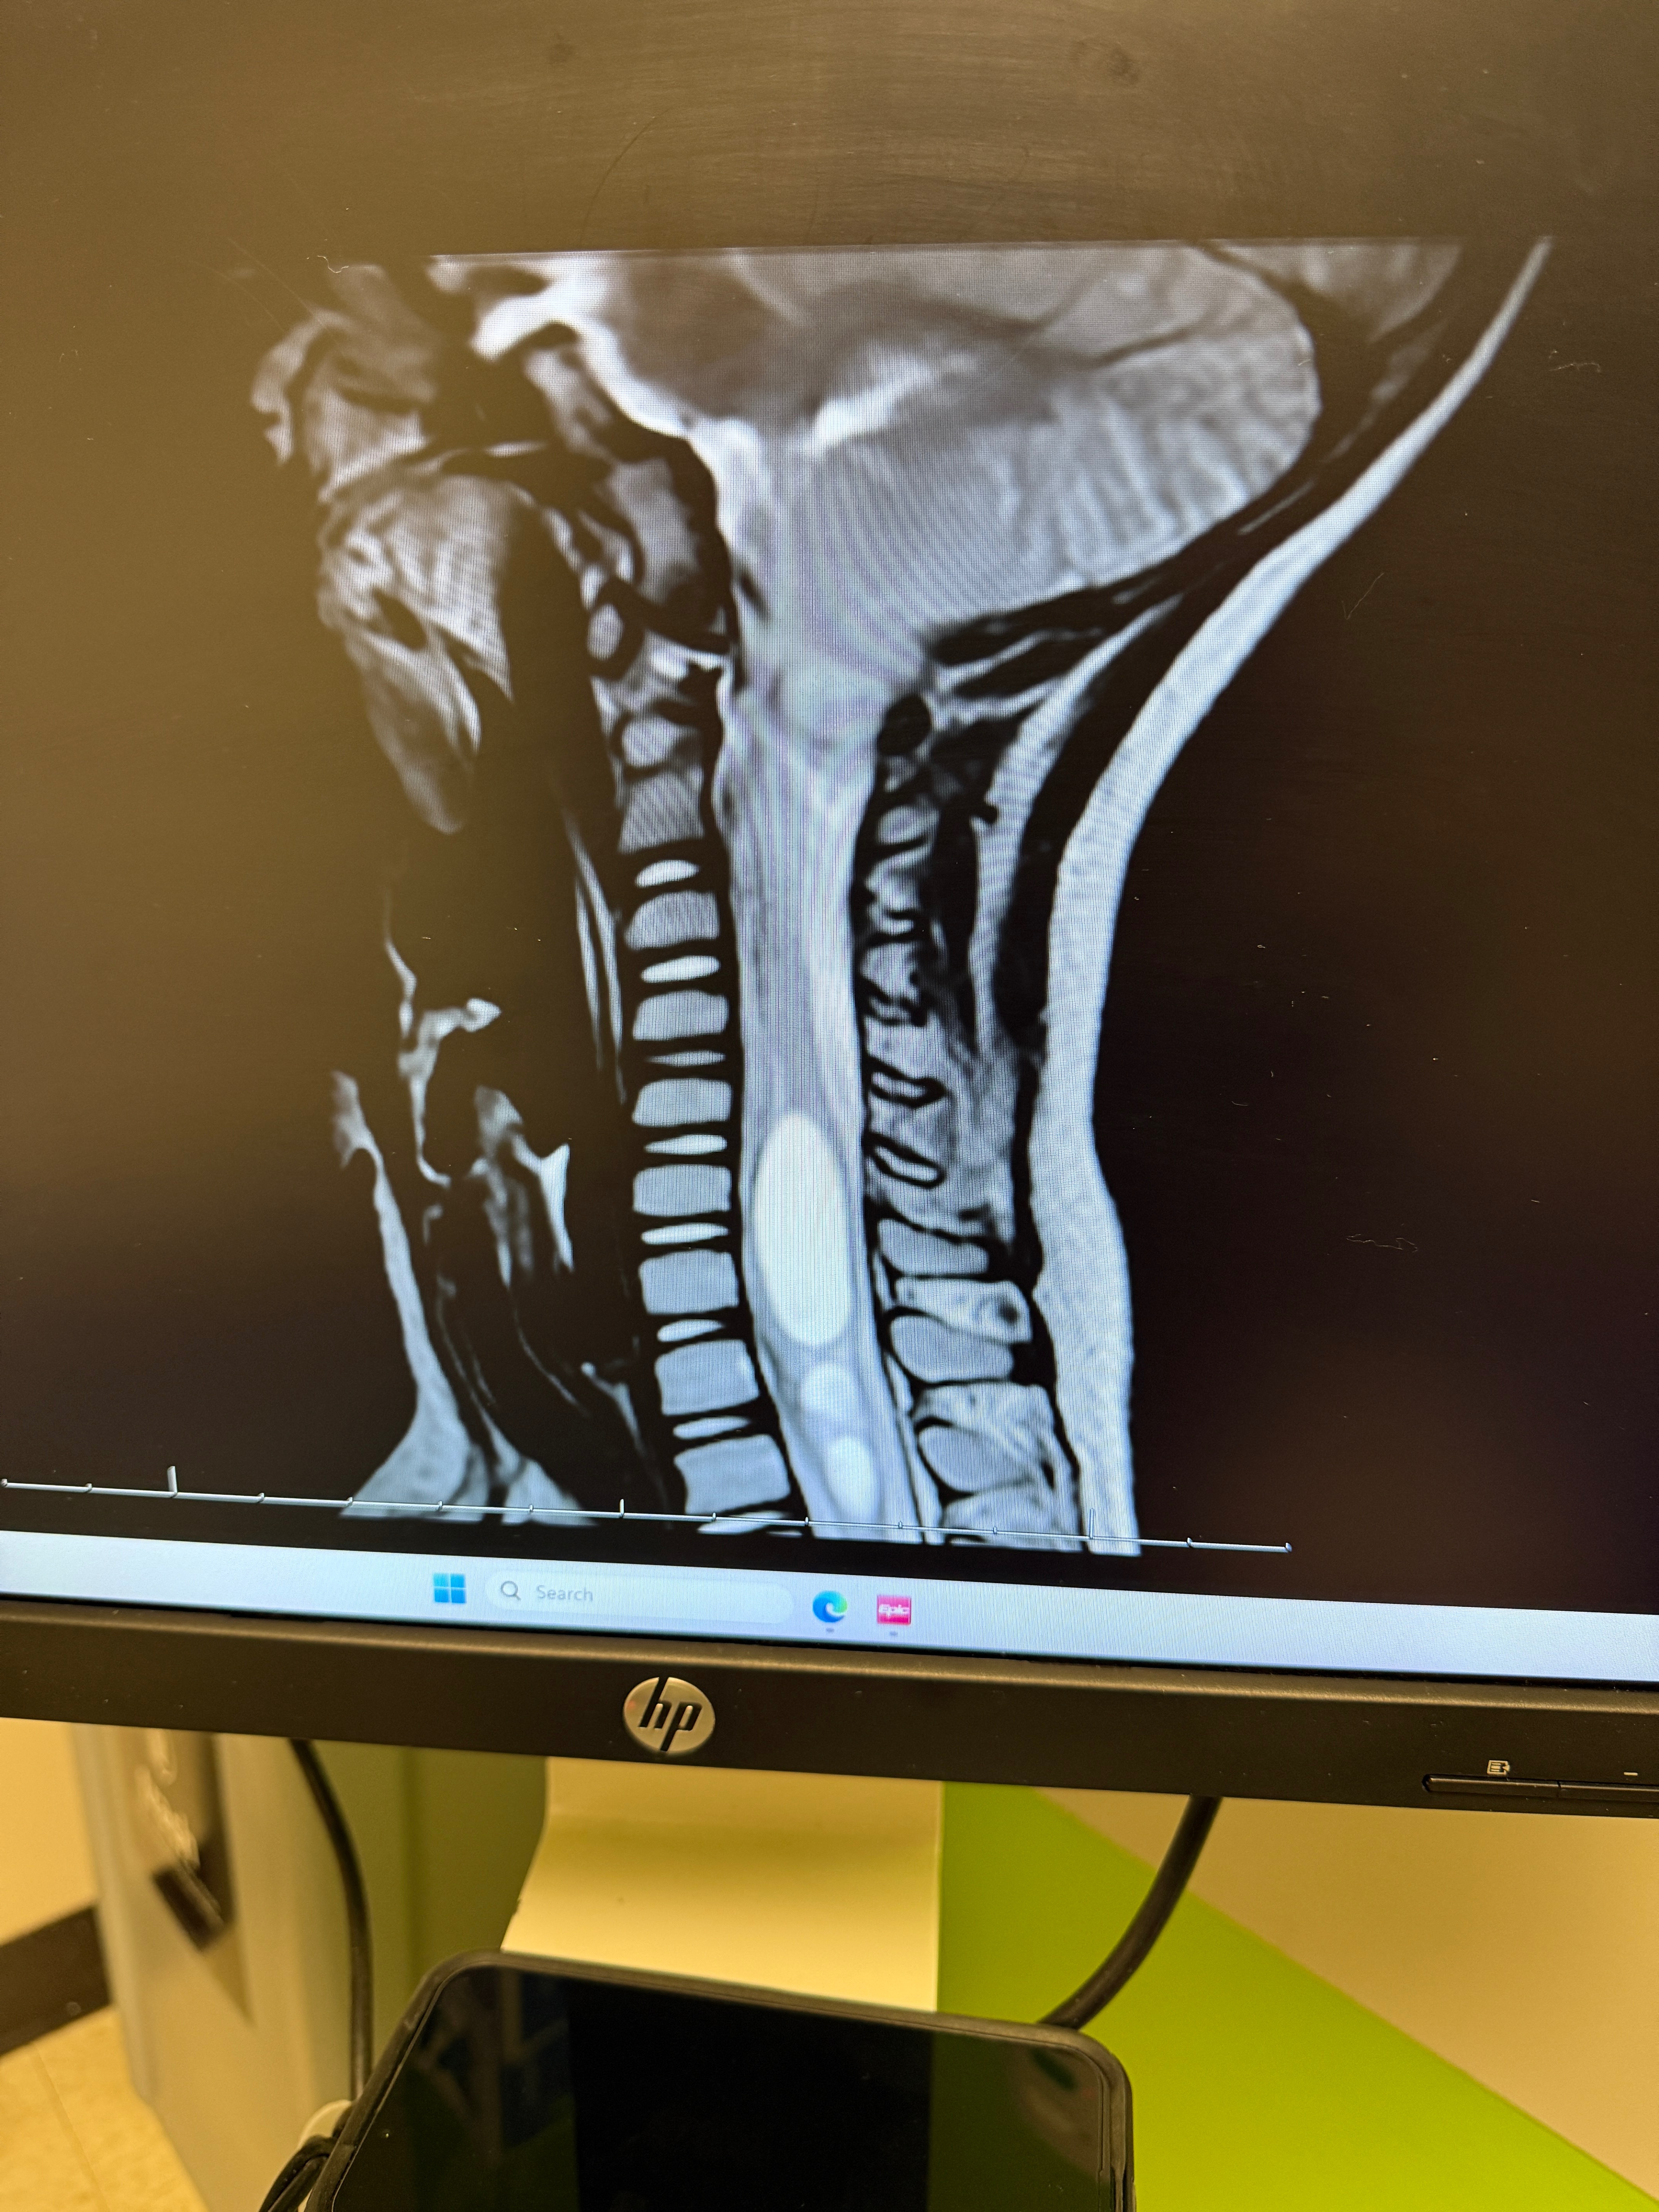

On June 24th Edgar had a MRI ordered by his eye doctor from having continuous eye pain over the last six months. What they found on the MRI was not what we were expecting at all. He was diagnosed with Arnold Chiari Malformation Type 1. We were told he had an over abundance of brain fluid, creating swelling in his brain and that we needed to follow up with a Neurosurgeon in LA.

The doctor explained how Edgar’s brain has slipped 22 mm down his spinal canal to his second vertebrae in his neck. He’s on heavy restriction till the surgery. He’ll be in ICU after surgery for a few days recovering. Once at home, he’ll be on bedrest for two weeks. He’ll sleep upright or slightly elevated for 6 weeks. He won’t be allowed to be submerged in water for 6 weeks as well. He has follow up appointments set after surgery on August 5th and September 9th both in LA.

The surgery is intense. They’ll be shaving down bone on his first 2 vertebrae in his neck and resecting part of his brain in the tonsillar cerebellum area and putting in a patch.